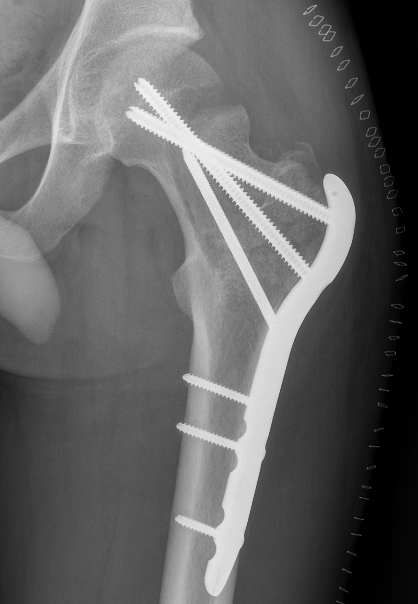

May allow surgical downstaging

- surgically unsalvageable / surgical treatment high morbidity

- arthrodesis or arthroplasty in young patients

Results

- prospective study of 20 patients with GCT

- pre-operative treatment with Denosumab

- pain relief in the first month

- improved radiological response with improved subchondral and cortical bone

- increased intra-lesional resection and joint preservation

- no effect on recurrence

Rutkowski et al Ann Surg Oncol 2015

- 222 patients at risk for wide resection treated with Denosumab

- allowed joint preservation in 96% of those thought to require joint replacement

- allowed joint preservation in 86% of those thought to require wide resection / arthrodesis

- recurrence rate 15%